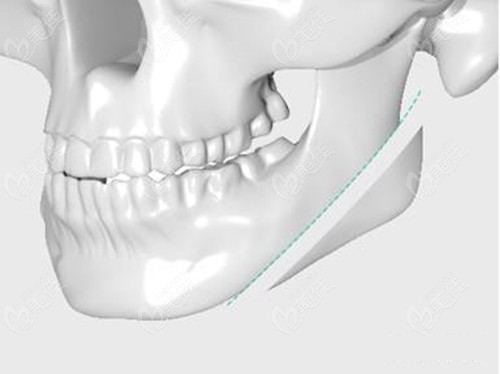

其次,潘宝华磨骨成效好,他做下颌角截骨手术使用的“磨截联合下颌角整形术”,不是单纯的下颌角切骨,而是磨骨+削骨联合进行,避免出现骨屑、二次留角、截骨部位不平整等问题,236z.c美佳om。网

术前会根据顾客的皮肤厚薄、骨骼情况选择适合的手术方式,截骨面平整度相对高一些,适合国字脸/下颌骨外翻等轮廓线条不流畅等人群。